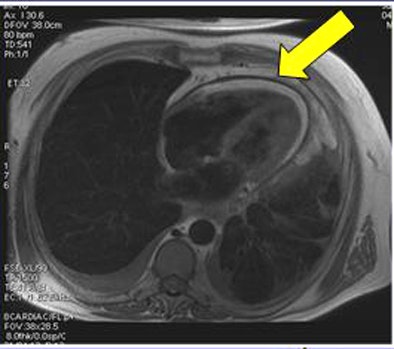

![]() |

| Above, thickened pericardium at MRI in patient with constrictive pericarditis. Below calcification of the pericardium is seen as a signal loss in the affected region. All images courtesy of Dr. Maryam Ghadimi Mahani. |